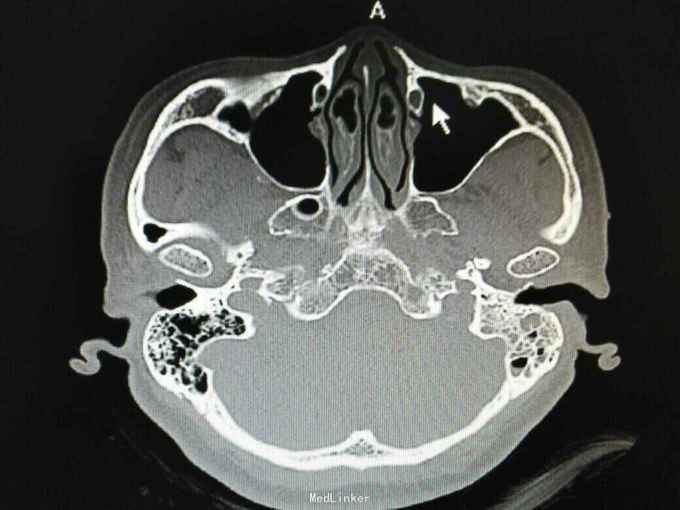

外耳道胆脂瘤,并 分泌性中耳炎? 胆固醇肉芽肿?

患者女性,47岁,以听力下降一周为主诉入院。 就诊后见外耳道后壁缺损,鼓室內积液,给予抗炎治疗后,鼓室內积液由缺损外耳道排出,呈棕褐色。 辅助检查:纯音听阈基本无听力损失。 诊断 外耳道胆脂瘤,并 分泌性中耳炎? 胆固醇肉芽肿? 治疗: 1.乳突根治术?乳突蜂房气化非常好,比较难做。 2.外耳道成型、后壁修补?